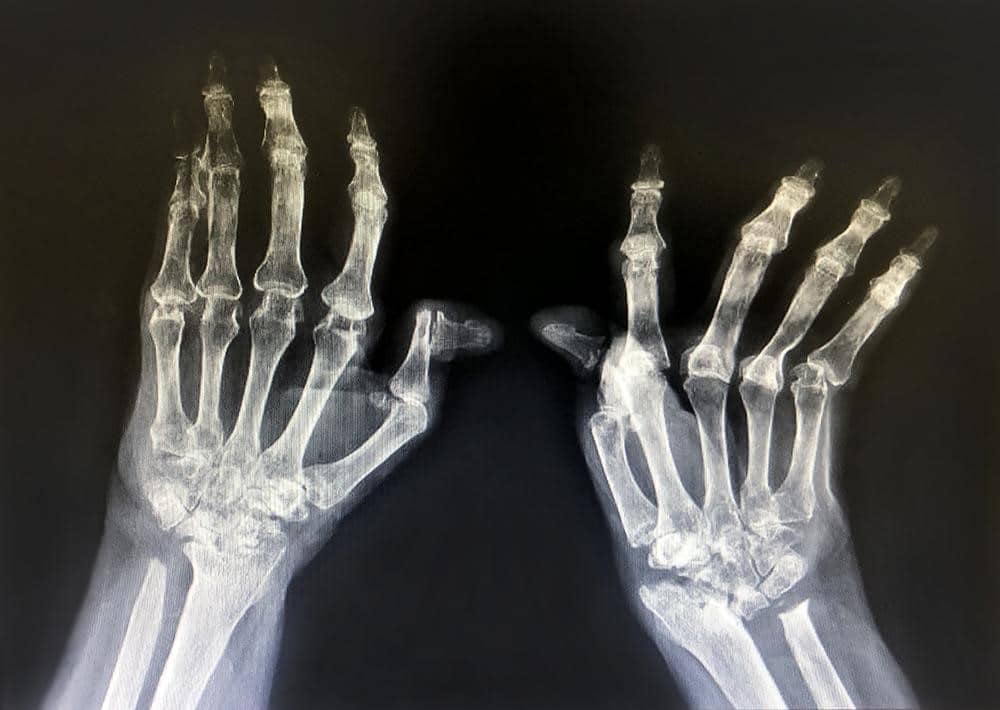

การตรวจทางภาพรังสีมีหลายวิธี โดยภาพถ่ายรังสี (Plain Radiography) จะเห็นการเปลี่ยนแปลงของข้อในผู้ป่วยที่โรคดำเนินมาระยะเวลาหนึ่งแล้ว การตรวจด้วยคลื่นเสียงความถี่สูง (Ultrasound) และการตรวจด้วยคลื่นแม่เหล็กไฟฟ้า (Magnetic Resonance Imaging; MRI) มีความไวกว่าภาพถ่ายรังสี และสามารถตรวจพบการอักเสบได้ในระยะแรกที่การตรวจร่างกายยังไม่ชัดเจน โดยแพทย์จะเป็นผู้พิจารณาเลือกการตรวจที่เหมาะสม

โรครูมาตอยด์ ระยะสุดท้ายภาพถ่ายรังสีมือของผู้ป่วยรูมาตอยด์ระยะสุดท้าย พบข้อและกระดูกถูกกัดกร่อนทำลายจนผิดรูป